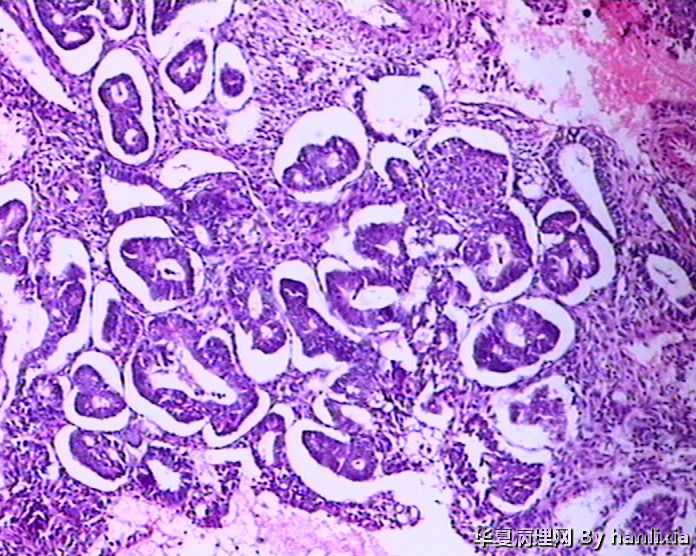

子宫内膜

标签:45岁女性 闭经1年 阴道出血10余天 行诊刮术。

复杂性增生伴不典型增生 局部癌变

患者45岁,闭经1年,阴道出血10余天,行诊刮术,未服用止血类药物。

腺体密集,背靠背及共壁现象,腺体有成角,腺上皮增生呈多层,有内折,腺体与间质比例大于1:1.

子宫内膜复杂性增生伴中-重度不典型增生,图1-2可疑癌变

支持复杂性增生伴不典型增生,细胞核淡染、核变圆,并见明显的核仁,有细胞学的不典型性